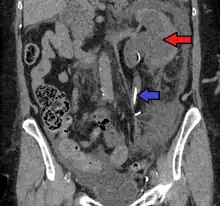

- CT scan of bilateral hydronephrosis due to a bladder cancer

- Massive hydronephrosis as marked by the arrow.